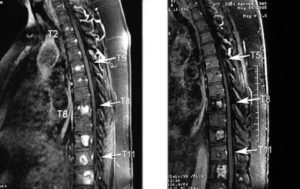

- Для выявления неврологии МРТ является лучшим вариантом обследования. Магниторезонансная томография показывает не только аномалии позвонков и межпозвоночных образований, она также нужна для исследования нервных стволов и расположенных в области позвоночника сосудов;

- Биопсия опухоли, для выявления ее типа, стадии развития и т.д.